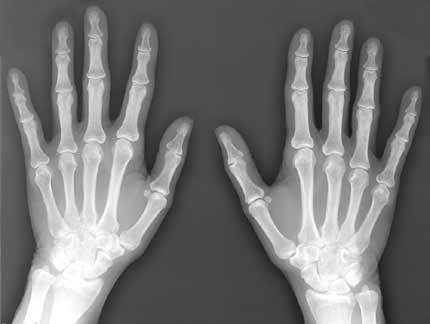

Röntgenstråling

- Oppdaget i 1895 av Wilhelm Conrad von Röntgen

- Röntgen-fotoner er svært energirike, med kort bølgelengde. De trenger derfor gjennom gjenstander som er ugjennomtrengelige for synlig lys.